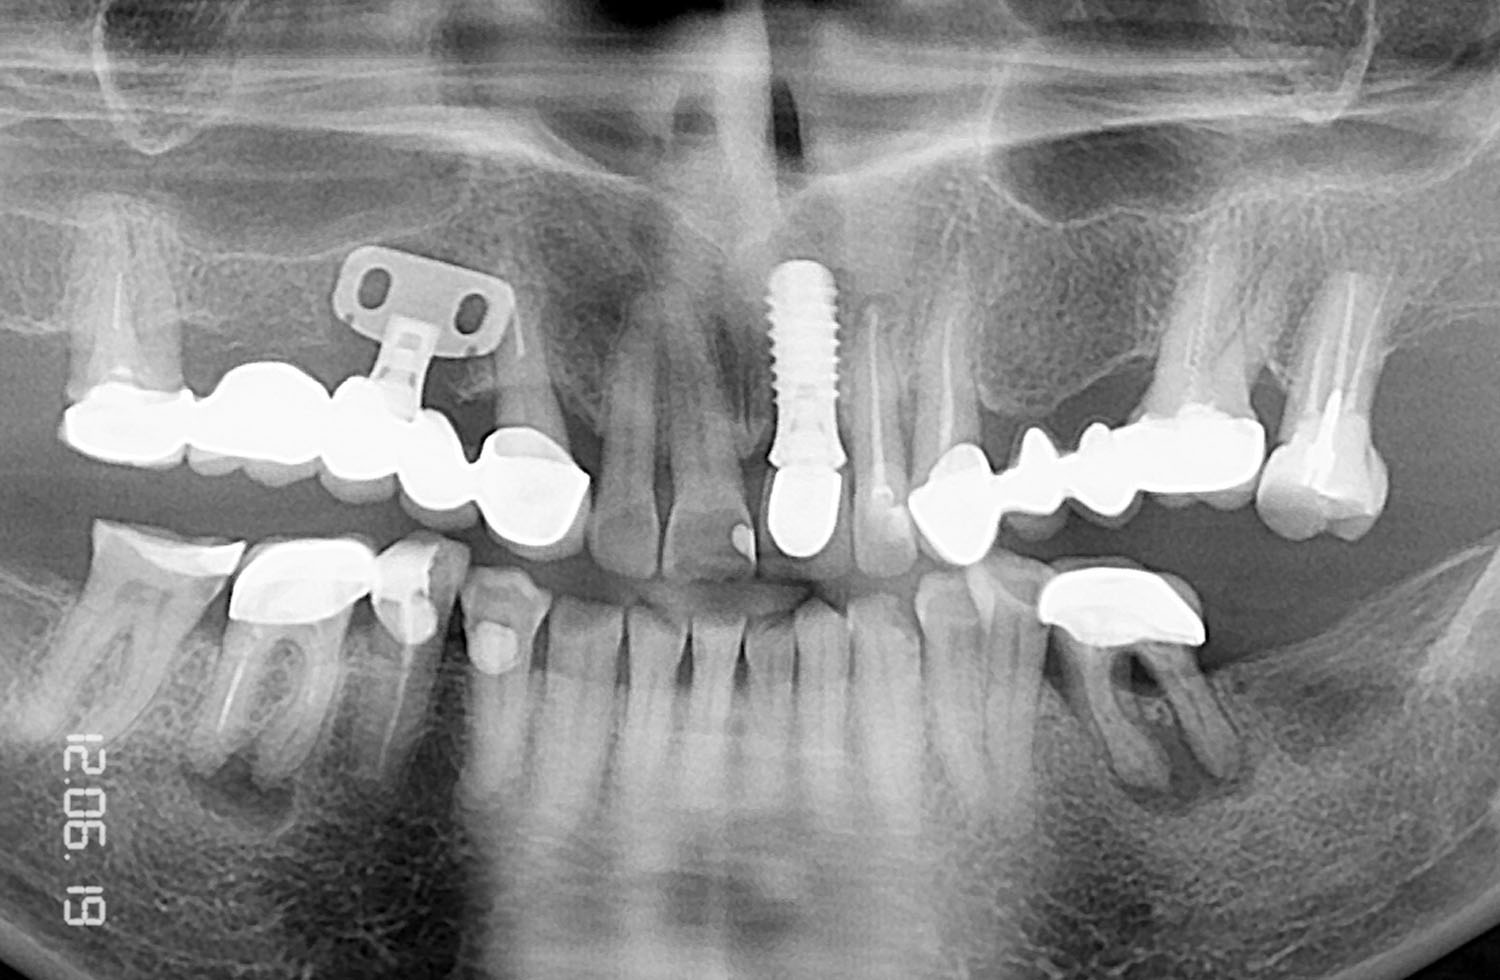

Контрольная рентгенограмм через 15 лет после операции. Если на рентгенограмме и можно различить небольшую щель между имплантатом и костью на уровне полированной части имплантата, то клинически она полностью отсутствует и не диагносцируется парадонтологическим зондом.

Для людей сомневающихся в правдивости и сроках - предлагаем два снимка из этой серии с оригинальными штампами даты